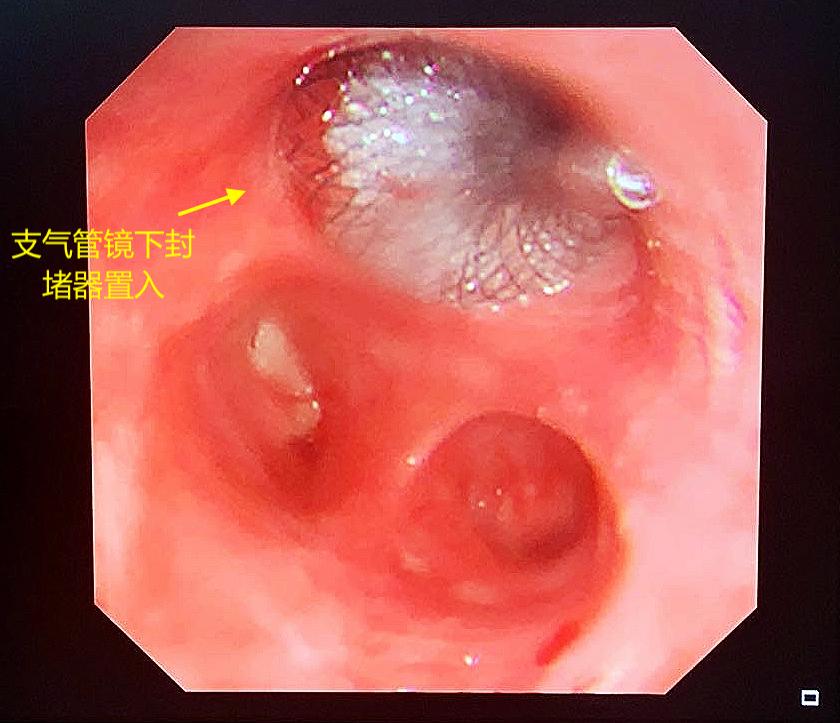

几经辗转,杜先生又去了河南一家医院。医生给他做了支气管镜下支架置入封堵术,手术一开始非常顺利。但是,术后复查拍片发现,右侧胸腔还是有很多积液,每天引流管仍然有几十毫升的脓液流出。

杜先生忐忑不安地等待了4个月,主治医生对他说,肺上的瘘口愈合不良,原来放进去的支架没用了,必须取出来。

NO.4 支气管镜下支气管瘘口封堵器置入术

镜支气管镜检查确定瘘口后,选择合适大小的金属封堵器置入封闭瘘口。但是单纯做封堵的失败率高,瘘口周围血运较差,没有软组织覆盖,内植物与周围组织愈合不良,加之脓腔未消灭,脓液刺激,导致瘘口扩大,封堵器松动失败。